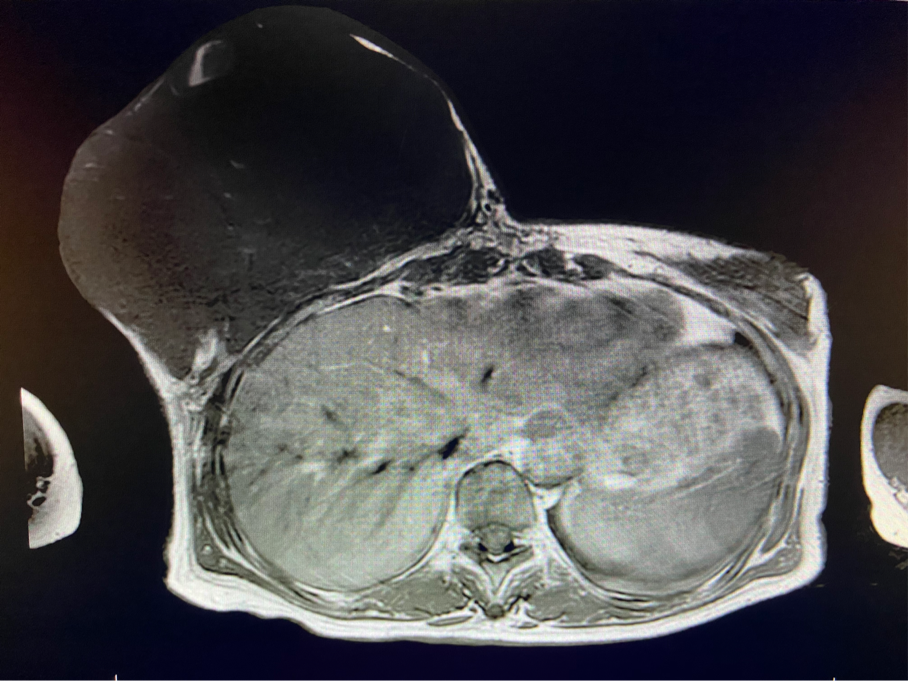

6個(gè)月前,王女士能感覺到右乳腫物明顯增大至“鴨蛋”一般,而且伴有局部皮膚瘙癢及輕度脹痛,可這次王女士并沒有那么幸運(yùn),服藥3個(gè)月不僅沒有控制住腫物,脹痛也越發(fā)嚴(yán)重,超聲檢查提示:右乳囊實(shí)性占位,最大前后徑約10.8cm,右腋窩多發(fā)腫大淋巴結(jié),遂行右乳腫物穿刺活檢術(shù),術(shù)后病理檢查提示:右乳腫物穿刺乳腺組織2條,均可見導(dǎo)管囊性擴(kuò)張,部分區(qū)域間質(zhì)纖維增生,其中1條內(nèi)導(dǎo)管上皮成普通型增生。輾轉(zhuǎn)當(dāng)?shù)囟嗉裔t(yī)院藥物治療后,錢沒有少花,但是療效甚微。

2周前,王女士的右乳外下方皮膚破潰,伴大量滲液,還發(fā)出陣陣惡臭。經(jīng)多方打聽,王女士從外地來到西安國際醫(yī)學(xué)中心醫(yī)院甲乳外科劉曉敏主任處就診。入院后,迅速完善了一系列相關(guān)術(shù)前檢查:王女士的雙乳外形不對(duì)稱,右乳約22?20cm,皮膚水腫明顯并可見靜脈曲張。右乳外下象限皮膚可見局部破潰,創(chuàng)面有3處,共約6?4cm大小,創(chuàng)面呈暗紅色,伴有血性滲出及惡臭,局部皮膚溫度升高。右側(cè)腋窩可觸及腫大淋巴結(jié)。

該患者右乳巨大腫物術(shù)前初步考慮乳腺葉狀腫瘤可能,因腫瘤太大,幾乎遍及整個(gè)右側(cè)乳房,為保證“無瘤原則”,術(shù)中切除范圍位置未知,極有可能出現(xiàn)皮瓣缺損。于是,經(jīng)過和整形醫(yī)院郭樹忠院長(zhǎng)、整形外科王愛武主任的討論,提供了兩種手術(shù)方式,一是創(chuàng)面修復(fù)(植皮或轉(zhuǎn)移皮瓣修復(fù)創(chuàng)面),二是乳房再造,與患者及家屬溝通后,決定先解決腫物,3年病情不再復(fù)發(fā)后,可以再考慮乳房重建。